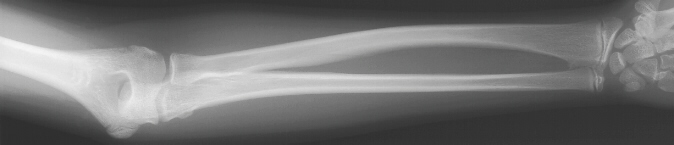

These were also noted in bilateral forearm films at the proximal and distal

poles.